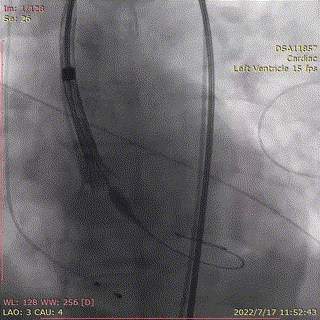

回收后,重新调整到工作位后,造影显示瓣膜位置良好,第2次0位释放,释放脱钩后瓣膜形态、位置良好,冠脉血流灌注正常,微少量瓣周漏,术后跨瓣压差降至0mmHg。

回收,调整位置

第二次0位释放

瓣膜有序脱钩

角度造影